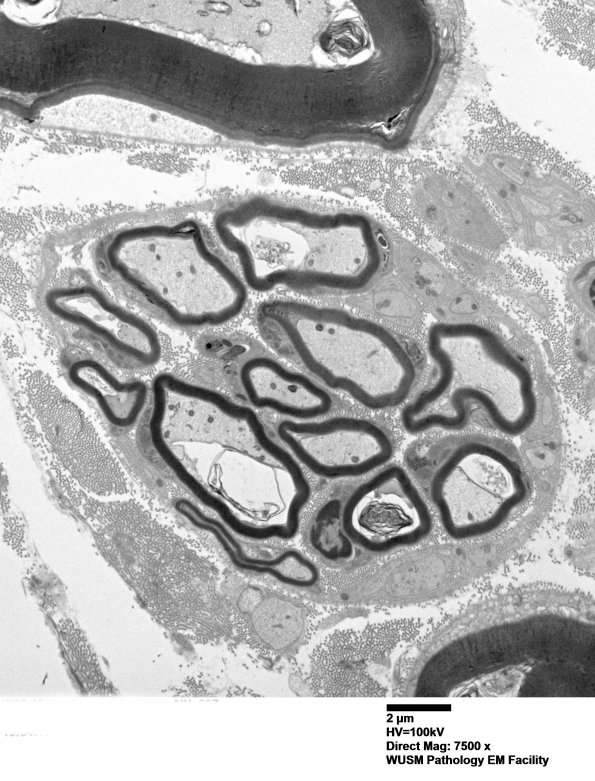

A number of clusters are well populated by small normal myelinated axons. (Electron micrograph)